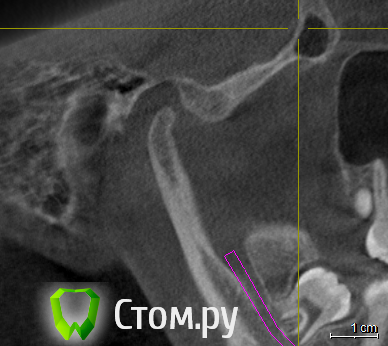

ElenaV Опубликовано 29 июня, 2014 Поделиться Опубликовано 29 июня, 2014 (изменено) Здравствуйте, дорогие доктора! У моей дочери 16ти лет проблема с ВНЧС. При ношении брекетов ей вытягивали нижнюю челюсть, выравнивали прикус и зубы , в частности - клыки выпирающие выравнивали. А через 1,5 года после снятия в одно прекрасное утро не смогла открыть рот. Нам советовали делать лазер, становилось легче. Так было 2 раза. А теперь по утрам, если спит на правой щеке, то челюсть правую заклинивает. Голова сильно болит в висках. Связано ли это с брекетами или другая причина может быть? У нас в Красноярске мы нашли доктора, который собрался нам помочь, поставить шины http://astreja.ru/uslugi/neyro-myshechnaya-stomatologiya. Может ли шина помочь решить эту проблему? В Красноярске выбор докторов небольшой, можно сказать - его нет. И уже просто страшно становится. Читая в интернете об этой проблеме, поняла, что это дело очень тонкое и непростое, испортить жизнь ребенку можно запросто. А еще советуют мануального терапевта. Куда пойти ? Может ли мануальный терапевт решить эти проблемы? Знакомый стоматолог сказал, что если челюсть поправят, то прикус может нарушится. А мануальный говорит - приходите - все исправим, даже снимков ему не надо. Теперь хочу выяснить у специалистов, как все таки поступить. К кому пойти сначала. Очень Вам буду благодарна за совет.Дорогие доктора, можете подсказать, что с суставом? Доктор сказал, что сустав находится далеко от височной кости, т.е. расстояние больше чем норма. Напишите, пожалуйста, что Вы видите на снимке, какую патологию. Вот еще сделала скриншоты суставов: левый и правый Вот еще правый сустав, немножко по другому Изменено 29 июня, 2014 пользователем ElenaV Ссылка на комментарий

Skip Опубликовано 29 июня, 2014 Поделиться Опубликовано 29 июня, 2014 Напишите, пожалуйста, что Вы видите на снимке, какую патологию. Эти КТ, с полуоткрытым ртом и выдвинутой челюстью, мало о чём говорят. У вас там что, уже стоит шина? Ссылка на комментарий

ElenaV Опубликовано 30 июня, 2014 Автор Поделиться Опубликовано 30 июня, 2014 (изменено) Эти КТ, с полуоткрытым ртом и выдвинутой челюстью, мало о чём говорят. У вас там что, уже стоит шина?Шины еще нет, мы сходили на прием, советуют ставить шину. Это КТ в 3Д делали с пластиной во рту, сказали - так надо. Что обычно так делают.Может поэтому и кажется доктору, что сустав неправильно в лунке стоит? Доктор сказал, что сустав далеко стоит от нормального местоположения. Поэтому выскакивает.Нужно МРТ сделать что бы точно понять? Или КТ переделывать? Изменено 30 июня, 2014 пользователем ElenaV Ссылка на комментарий

Force Опубликовано 1 июля, 2014 Поделиться Опубликовано 1 июля, 2014 с восковым шаблоном это по Маклафлину в ЦС сделано КТ. 1 Ссылка на комментарий

ElenaV Опубликовано 1 июля, 2014 Автор Поделиться Опубликовано 1 июля, 2014 с восковым шаблоном это по Маклафлину в ЦС сделано КТ. А как понять по этому КТ, правильно ли стоит сустав? Если рот открытый на снимке? Ссылка на комментарий

Skip Опубликовано 1 июля, 2014 Поделиться Опубликовано 1 июля, 2014 с восковым шаблоном это по Маклафлину в ЦС сделано КТ. Понятно. Ну тогда и с привычной окклюзией стоило бы сравнить, т.е. два снимка, а вернее три, если добавить макс. открытие рта. 1 Ссылка на комментарий